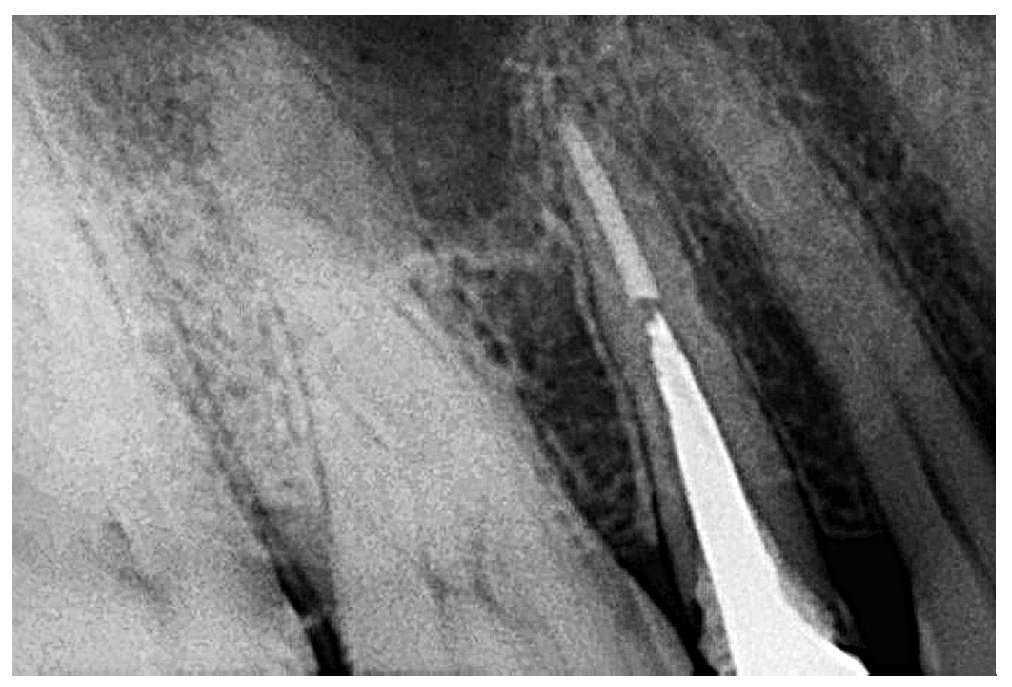

En la segunda sesión, al cabo de 4 días, se determinó la longitud de trabajo y se pudo finalizar el tratamiento endodóntico sin que surgieran más complicaciones (fig. 3). En un primer momento se restauró el diente con una obturación de amalgama y al cabo de 1 semana se colocó una corona de resina provisional. El diente quedó asintomático al cabo de 3 meses y la paciente pudo ser remitida al especialista para iniciar el tratamiento definitivo (fig. 4).

Figura 3. Radiografía de control obtenida inmediatamente después de la obturación. En apical se detecta una sobreobturación.